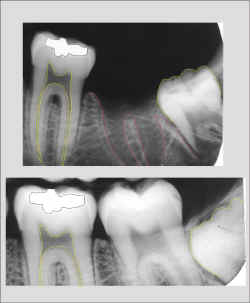

espaco2.gif (821 bytes)Radiografia da ossada

espaco2.gif (821 bytes)Região de molares inferiores esquerdos evidenciando perda provavelmente post-mortem do dente 47.

espaco2.gif (821 bytes)Observe que a forma alveolar e conseqüentemente das raízes perdidas estão evidentes.

espaco2.gif (821 bytes)A rizogênese incompleta do dente 48 permitiu a estimativa da idade.

espaco2.gif (821 bytes)Radiografia do suspeito obtida intra-vitae e encaminhada ao IML pelo Cirurgião Dentista que cumpriu seu papel arquivando os exames complementares no prontuário odontológico. Parabéns ao CD.

espaco2.gif (821 bytes)Confirmação da Identificação positiva pela comparação computadorizada da segunda radiografia.

espaco2.gif (821 bytes)Observe as peculiaridades da imagem de radiodensidade metálica. Na verdade são duas restaurações cujas imagens se superpuseram, uma oclusal e outra vestibular.

espaco2.gif (821 bytes)Observe o número de cúspides do molar incluso.

espaco2.gif (821 bytes)O intervalo de tempo entre a radiografia intra-vitae e a época da morte calculada é compatível com a erupção ocorrida.